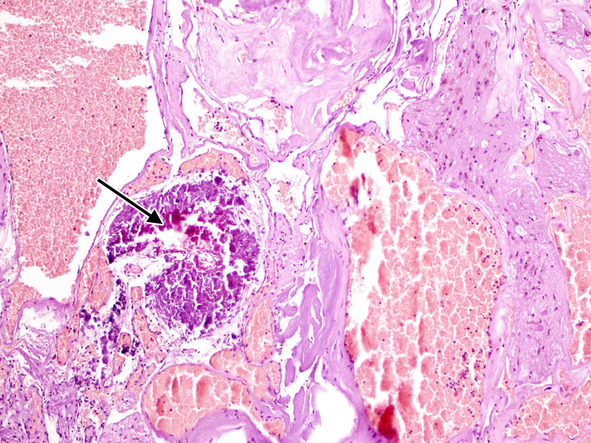

В ткани КМ могут быть обнаружены участки кальцификации, гиалиноза стенок (рис. 14).

Довольно часто в строме встречаются признаки повторных кровоизлияний в виде остатков гематом различной давности. По периферии каверномы часто можно обнаружить фрагменты капсулы, типичной для хронической гематомы (рис. 15).

Рис. 13. Тромбоз и склероз сосудистых полостей в «классической» кавернозной мальформации. Ув. х 200

Рис. 14. Кальцификат (стрелка) и склеротические изменения в стенках сосудистых полостей. Ув. х 100

Рис. 15. А. Начальная стадия формирования стенки гематомы – скопления макрофагов, нагруженных гемосидерином. Ув. х 400. Б. Сформировавшаяся капсула гематомыс отложениями гемосидерина, лимфоплазмоцитарной инфильтрацией и новообразованными сосудами. Ув. х 200